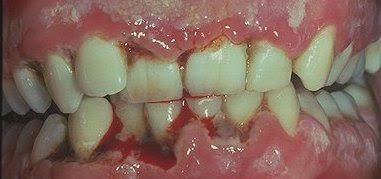

d. The interdental papillae are blunted, inflamed, edematous and hemorrhagic. Show Punched out crater like necrotic areas covered by grayish pseudo membrane

– Interdental papillae show surface ulceration covered by a fibrinopurulent membrane.

– Underlying connective tissue shows acute/mixed inflammatory infiltrate along with extensive hyperemia.